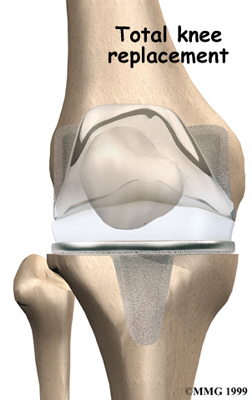

Artificial Knee Replacement

An artificial knee replacement is the ultimate solution for advanced knee OA.

Surgeons prefer not to put a new knee joint in patients younger than 60. This is because younger patients are generally more active and might put too much stress on the joint, causing it to loosen or even crack. A revision surgery to replace a damaged prosthesis is harder to do, has more possible complications, and is usually less successful than a first-time joint replacement surgery.

Related Document: FYZICAL Green Brook's Guide to Artificial Joint Replacement of the Knee